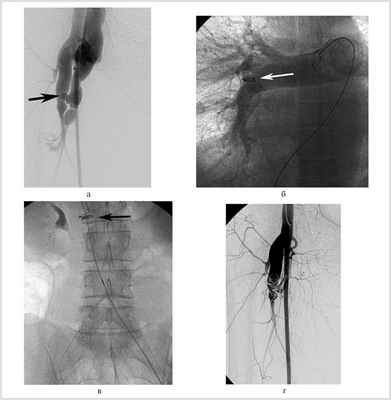

Во время выполнения разобщения травматического артериовенозного свища глубокой артерии бедра произошла миграция окклюзирующей спирали через свищ в легочную артерию. Откуда она была извлечена с помощью петли и корзинки Дормиа. Диаметр свища был 6 мм, имплантируемой спирали — 10 мм, однако из-за эластичности краев артериовенозного соустья, большого градиента давления спираль дислоцировалась в вену. Последующая окклюзия была начата двумя спиралями диаметром 15 мм, а затем дополнена двумя спиралями диаметром 10 мм (рис. 4).

Рис. 4. Травматический артериовенозный свищ глубокой артерии бедра со сбросом в бедренную вену. Рентгеноэндоваскулярная окклюзия артериовенозного соустья между глубокой артерией бедра и бедренной веной. Дислокация спирали.

Для разобщения соустья между аортой и левой почечной веной было использовано 2 окклюдера — Amplatzer ASD и Plug. Артериовенозный сброс был ликвидирован, проявления сердечной недостаточности значительно уменьшились. В раннем послеоперационном периоде развился тромбоз нижней полой вены, что потребовало установки кава-фильтра и выполнения тромбэктомии [5].